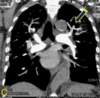

TC en TEP

Es diagnóstica, nos permite ver el trombo

95

TEP

96

4 = trombo

97